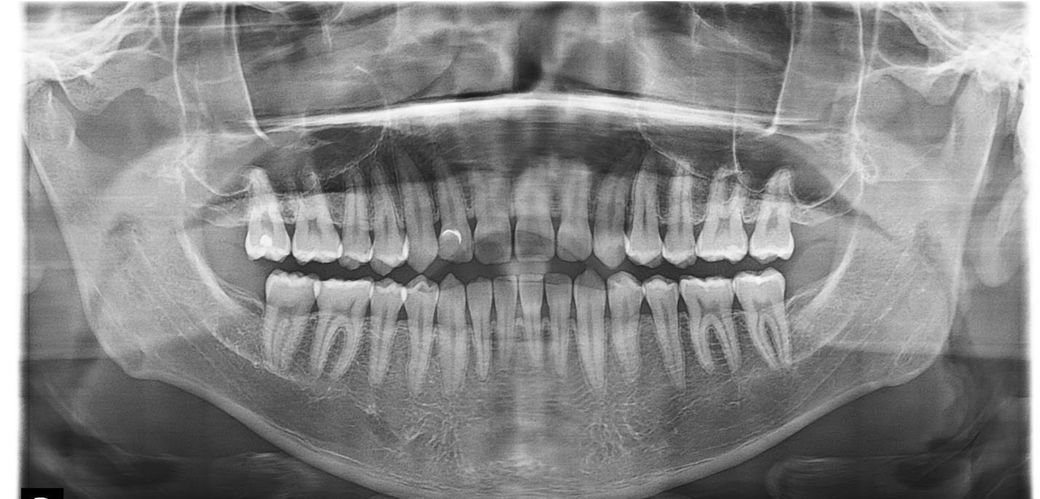

엑스레이 찍었어요 충치가 있다고 하는데 과잉진료인지 궁금해요

첫 번째 사진 치과는 스케일링 받으면서 xray도 같이 찍었는데 어금니 양쪽에 인접면 충치 인레이 2개를 해야된다고 해서

두 번째 사진 치과를 갔는데 오른쪽 어금니 인레이3개 왼쪽 인레이 1개 아랫니 레진 1개를 부르더라고요

둘다 과잉 진료인가요? 서로 진료가 달라서 의심스럽고 통증도 없구요 두 번째 사진은 치아 사진도 보여주면서 여기 검은 색 인접면 보여주긴 했는데 솔직히 뭐가 뭔지 모르겠고 통증도 없고 20대인데 굳이 치아 절삭이 필요한가 싶어서 문의드려요

2. 인접면 충치가 위 엑스레이상에서 보이는 상태입니다 엑스레이상 보이는 충치는 이미 진행이 된 충치여서 그대로 둔다고 나아지고 그런건 없습니다.